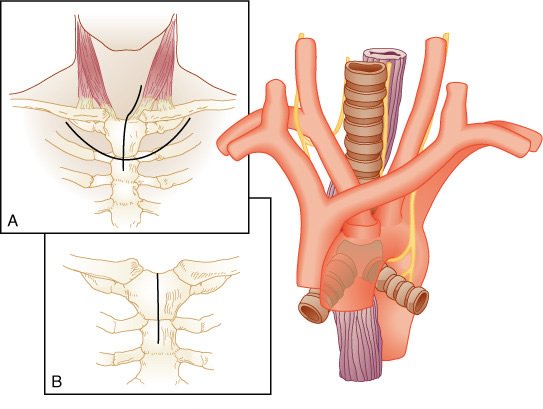

Exposição do esôfago torácico superior através de uma esternotomia parcial superior. Ë demonstrado o trajeto do nevo laríngeo recorrente esquerdo pelo arco aórtico, e daí para o sulco traqueoesofágico.

A, A incisão cervical esquerda habitual estendida até a porção anterior do tórax na linha média, bem como a curva alternativa da incisão torácica anterior de pele evitam a formação de fibrose cicatricial na porção inferior do pescoço.

B, A incisão da esternotomia se estende da fúrcula supra-esternal através do manúbrio e atravessa o ângulo de Louis.